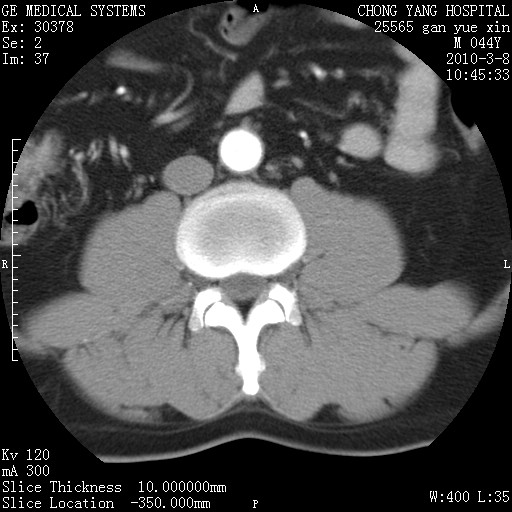

标题: CT24940:主动脉增强,典型病例。 [打印本页]

标题: CT24940:主动脉增强,典型病例。

夹层动脉瘤。

动脉夹层

夹层动脉瘤,典型

主动脉夹层。

动脉夹层的分型:

⒈debakey分型:根据主动脉夹层累及部位,分为三型:ⅰ型:原发破口位于升主动脉或主动脉弓部,夹层累及升主动脉、主动脉弓部、胸主动脉、腹主动脉大部或全部,少数可累及髂动脉。ⅱ型:原发破口位于升主动脉,夹层累及升主动脉,少数可累及部分主动脉弓。ⅲ型:原发破口位于左锁骨下动脉开口远端,根据夹层累及范围又分为ⅲa,ⅲb。ⅲa型:夹层累及胸主动脉。ⅲb型:夹层累及升主动脉、腹主动脉大部或全部。少数可累及髂动脉。

⒉stanford分型:a型:夹层累及升主动脉,无论远端范围如何。b型:夹层累及左锁骨下动脉开口以远的降主动脉。

夹层动脉瘤,少量胸水

夹层动脉瘤;左侧少量胸腔积液。

典型主动脉夹层。